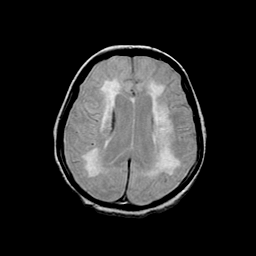

Basal Ganglia Calcification: proton density-weighted MR -- Slice #11

[Home][Help][Clinical] Slice 11